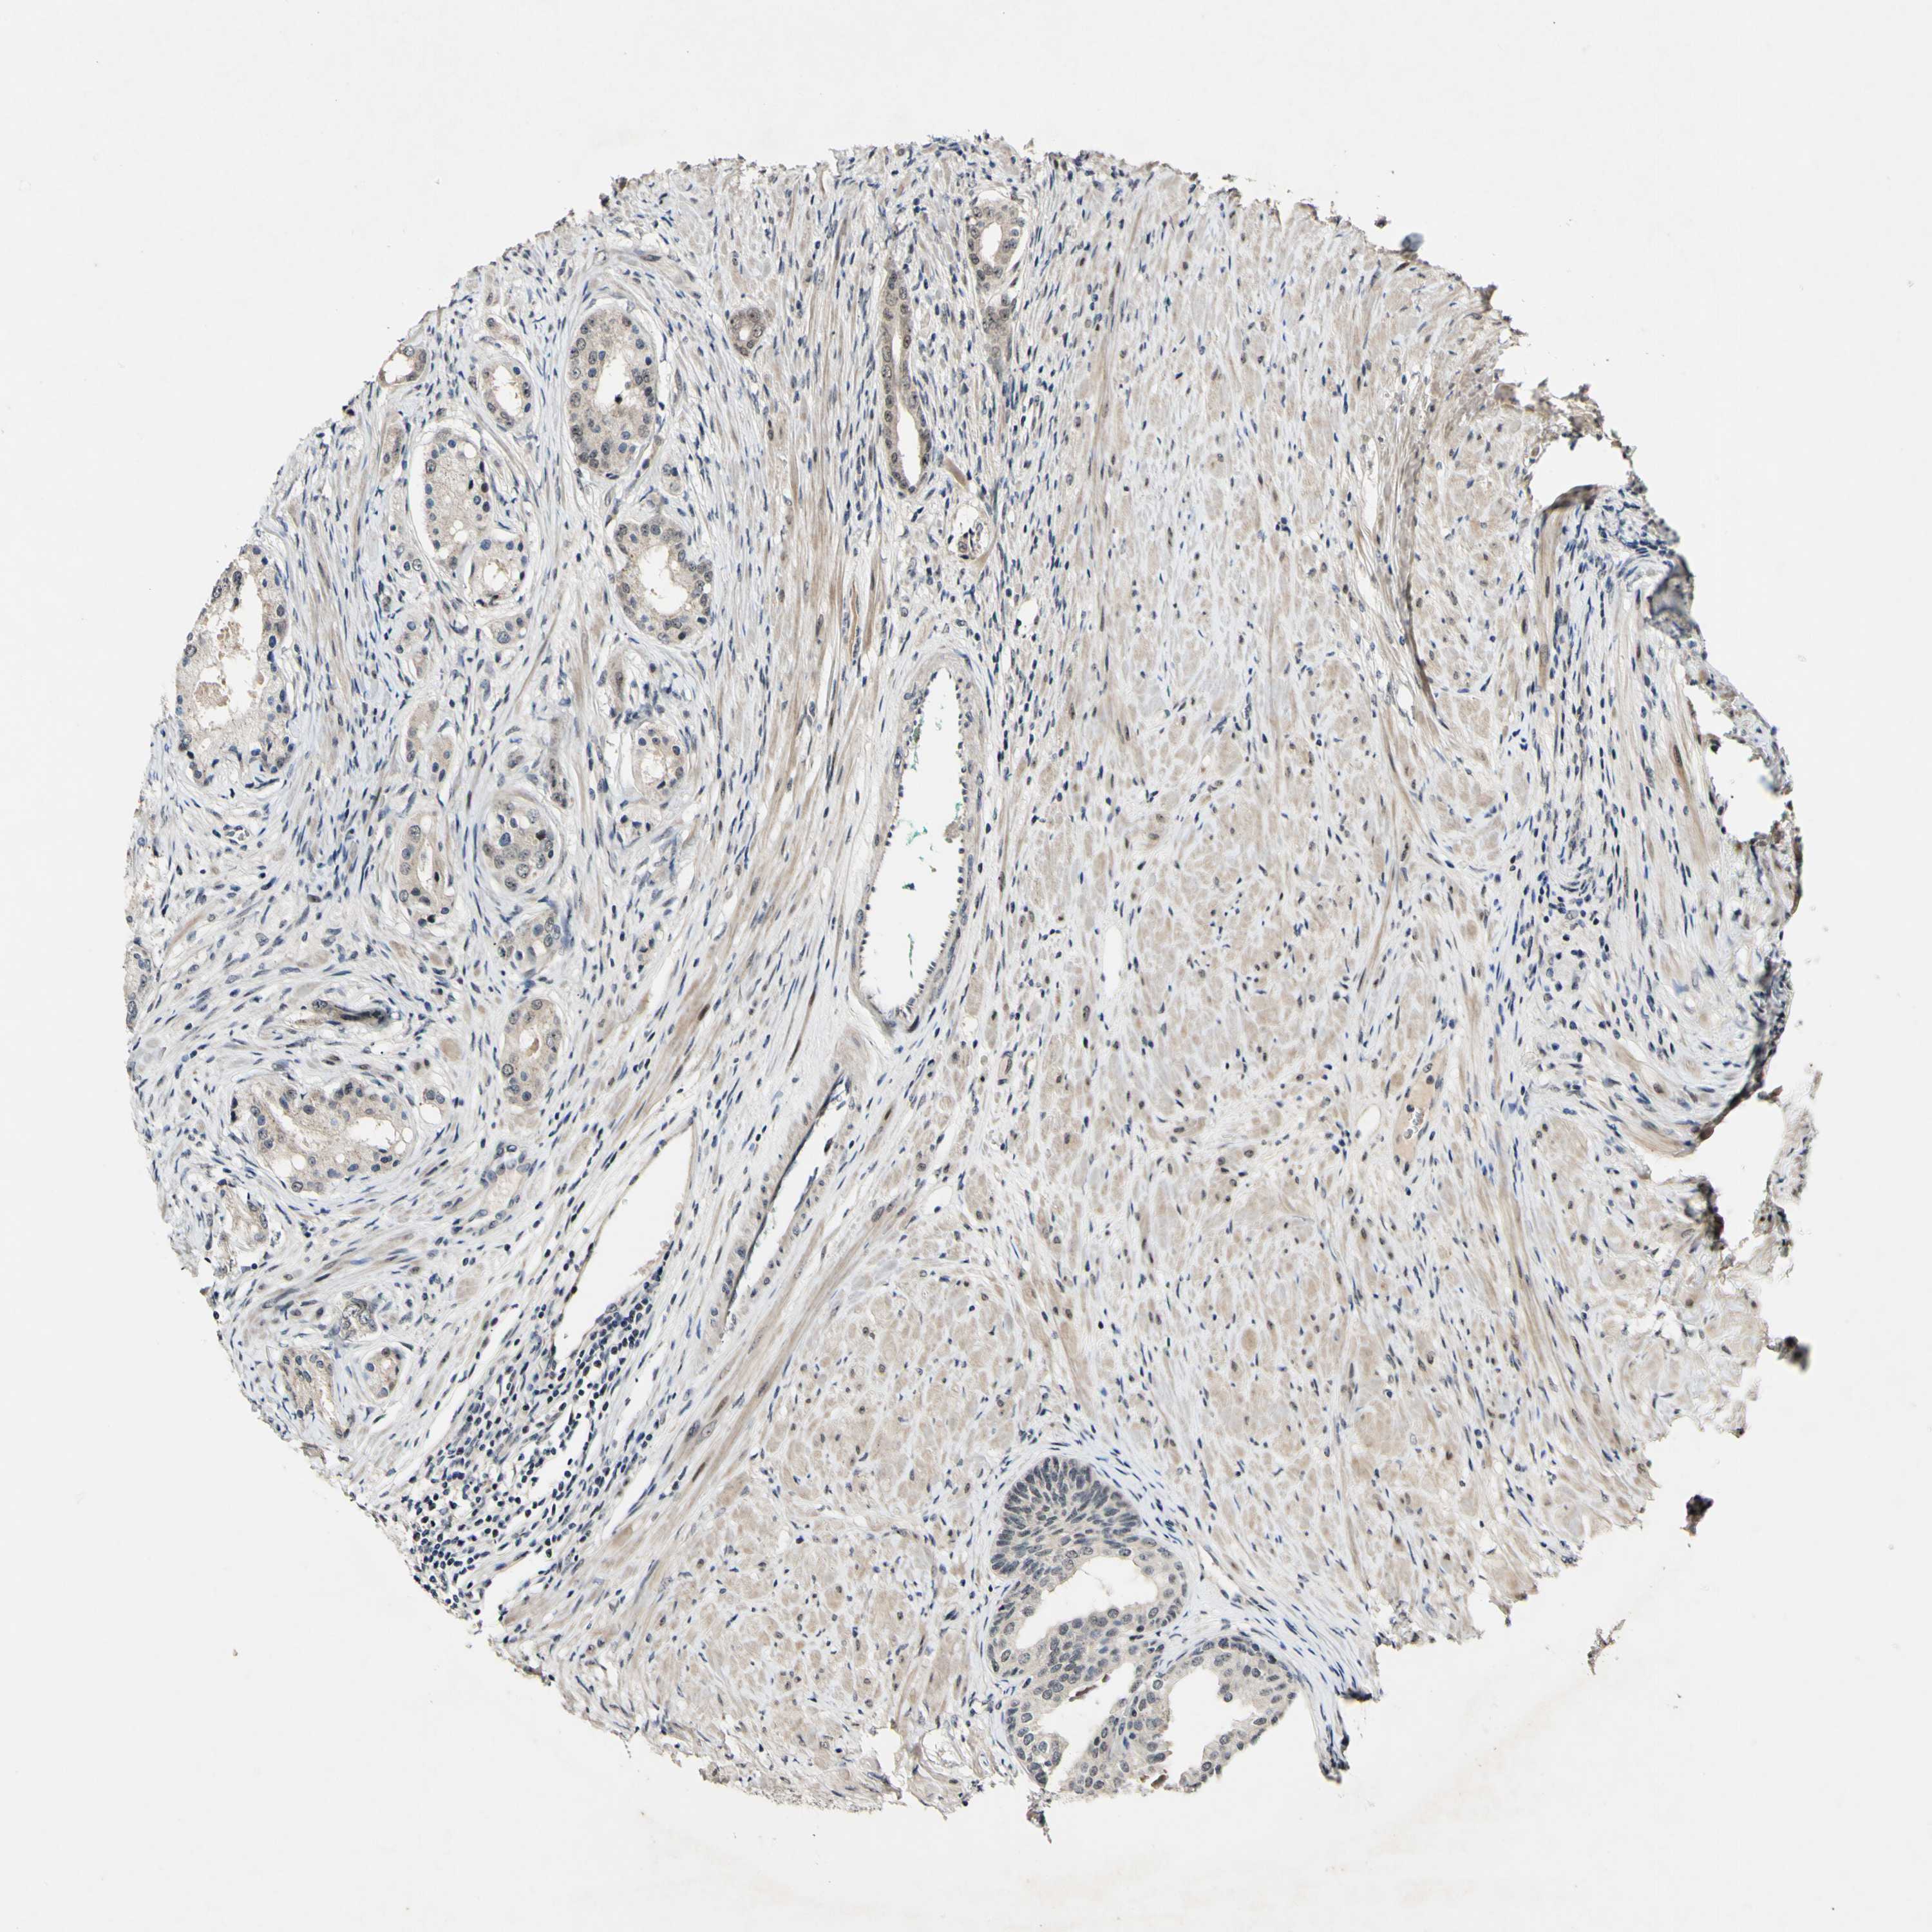

PROSTATE CANCER - Protein expressioni

A mouse-over function shows sample information and annotation data. Click on an image to view it in a full screen mode. Samples can be filtered based on level of antibody staining by selecting one or several of the following categories: high, medium, low and not detected. The assay and annotation is described here.

Antibody stainingi

Antibody staining in the annotated cell types in the current human tissue is reported as not detected, low, medium, or high, based on conventional immunohistochemistry profiling in selected tissues. This score is based on the combination of the staining intensity and fraction of stained cells.

Each image is clickable and will lead to virtual microscopy that enables deeper exploration of all samples and also displays staining intensity scores, fraction scores and subcellular localization as well as patient and tissue information for each sample.

Antibody HPA000827

Staining

High

Medium

Low

Not detected

Intensity

Strong

Moderate

Weak

Negative

Quantity

>75%

75%-25%

<25%

None

Location

Nuclear

Cytoplasmic/membranous

Cytoplasmic/membranous,nuclear

Adenocarcinoma, Low grade